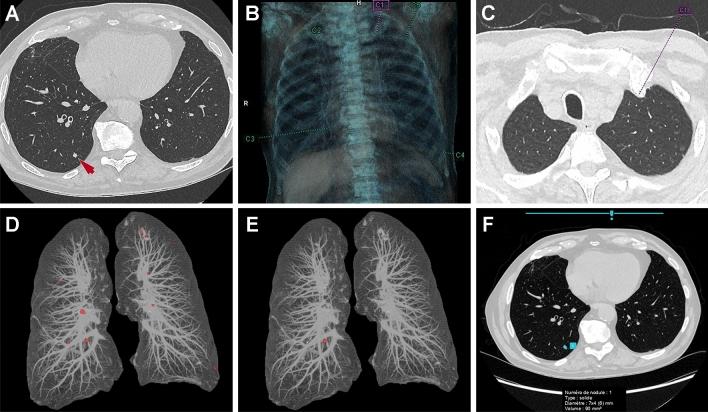

Artificial intelligence (AI) has been a very active research topic over the last years and thoracic imaging has particularly benefited from the development of AI and in particular deep learning. We have now entered a phase of adopting AI into clinical practice. The objective of this article was to review the current applications and perspectives of AI in thoracic oncology. For pulmonary nodule detection, computer-aided detection (CADe) tools have been commercially available since the early 2000s. The more recent rise of deep learning and the availability of large annotated lung nodule datasets have allowed the development of new CADe tools with fewer false-positive results per examination. Classical machine learning and deep-learning methods were also used for pulmonary nodule segmentation allowing nodule volumetry and pulmonary nodule characterization. For pulmonary nodule characterization, radiomics and deep-learning approaches were used. Data from the National Lung Cancer Screening Trial (NLST) allowed the development of several computer-aided diagnostic (CADx) tools for diagnosing lung cancer on chest computed tomography. Finally, AI has been used as a means to perform virtual biopsies and to predict response to treatment or survival. Thus, many detection, characterization and stratification tools have been proposed, some of which are commercially available.

人工智能(AI)是近年来非常活跃的研究课题,特别是在胸部影像学领域,AI 技术,尤其是深度学习技术,得到了广泛的应用。现在,我们已经进入了将 AI 应用于临床实践的阶段。本文的目的是回顾 AI 在胸部肿瘤学中的当前应用和前景。在肺结节检测方面,自 21 世纪初以来,计算机辅助检测(CADe)工具已经商业化。深度学习的兴起以及大型注释肺结节数据集的可用性,使得开发出了新的 CADe 工具,每个检查的假阳性结果更少。经典的机器学习和深度学习方法也被用于肺结节分割,从而实现了结节体积和肺结节特征的定量分析。在肺结节特征分析方面,使用了放射组学和深度学习方法。国家肺癌筛查试验(NLST)的数据允许开发几种计算机辅助诊断(CADx)工具,用于在胸部 CT 上诊断肺癌。最后,人工智能还被用作进行虚拟活检以及预测治疗反应或生存的手段。因此,已经提出了许多检测、特征分析和分层工具,其中一些已经商业化。